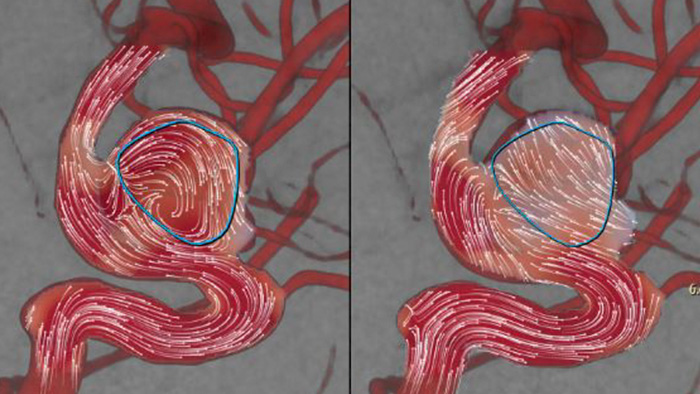

AneurysmFlow

AneurysmFlow is designed to give you relevant information before and after flow diverter deployment. It visualizes and quantifies flow changes for greater confidence in procedural effectiveness.